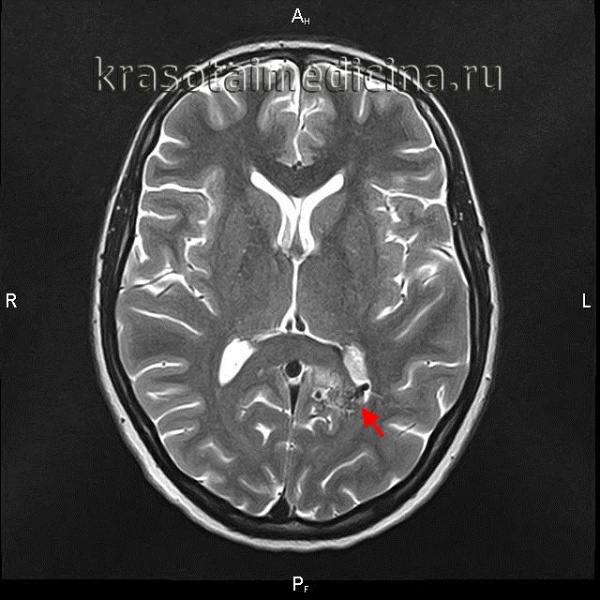

Поводом для обращения к неврологу до разрыва АВМ могут быть упорные головные боли, впервые возникший эпиприступ, появление очаговой симптоматики. Пациенту проводится плановое обследование, включающее ЭЭГ, Эхо-ЭГ и РЭГ. При разрыве АВМ диагностика осуществляется в экстренном порядке. Наиболее информативны в диагностике сосудистых мальформаций томографические методы. Компьютерная томография и магнитно-резонансная томография могут быть использованы как для визуализации тканей мозга, так и для исследования сосудов. В случае разрыва АВМ МРТ головного мозга более информативно, чем КТ. Она дает возможность выявить локализацию и размер кровоизлияния, отдифференцировать его от других объемных интракраниальных образований (хронической гематомы, опухоли, абсцесса головного мозга, церебральной кисты).

При торпидном течении АВМ МРТ и КТ головного мозга могут оставаться в норме. Обнаружить сосудистую мальформацию в таких случаях позволяет лишь церебральная ангиография и ее современные аналоги — КТ сосудов и МР-ангиография. Исследования церебральных сосудов проводятся с использованием контрастных веществ. Диагностика осуществляется нейрохирургом, который также оценивает операционный риск и целесообразность хирургического лечения АВМ. При этом следует учитывать, что при разрыве, в связи с компрессией сосудов в условиях гематомы и отека мозга, томографический размер АВМ может быть существенно меньше реального.